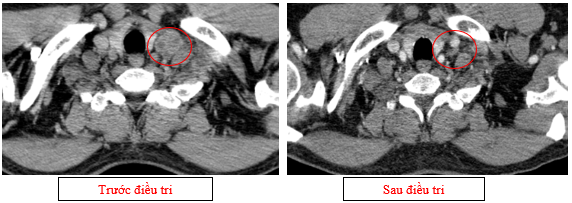

-         Siêu âm hạch vùng cổ (11/2025): Góc hàm hai bên có vài hạch kích thước lớn nhất 6mm.

-         Chụp cắt lớp vi tính lồng ngực (11/2025): Màng phổi vùng rốn phổi trái dày,dày tổ chức kẽ vùng ngoại vi đáy phổi hai bên. Màng phổi trái có vài nốt đặc ngấm thuốc nốt lớn nhất kích thước 17x15mm. Khoang màng phổi hai bên không có dịch – khí (Tổn thương giảm đáng kể so với phim chụp 08/2025). Trung thất, rốn phổi hai bên, hố thượng đòn trái có vài hạch, hạch lớn nhất kích thước 12x6mm. Vài nốt đặc xương rải rác thân đốt sống, các cung xương sườn hai bên.

Hình 07: Hạch thượng đòn trái giảm đáng kể kích thước, từ 22mm còn 7mm sau điều trị.

-         Chụp cắt lớp vi tính ổ bụng (11/2025): Nhu mô gan phải có vài nốt, nốt lớn nhất hạ phân thùy VII có nốt giảm tỷ trọng, ngấm thuốc kém sau tiêm đường kính 8mm, hạ phân thùy II, III có nốt giảm tỷ trọng đường kính (tổn thương giảm đáng kể so với phim chụp ngày 08/2025). Các ổ đặc xương rải rác đốt sống ngực thắt lưng, xương cùng và xương chậu hai bên.

Hình 11: Tổn thương ngấm thuốc kém nhu mô gan hạ phân thùy II giảm đáng kể kích thước

Hình 12: Tổn thương ngấm thuốc kém nhu mô gan hạ phân thùy VII giảm đáng kể kích thước